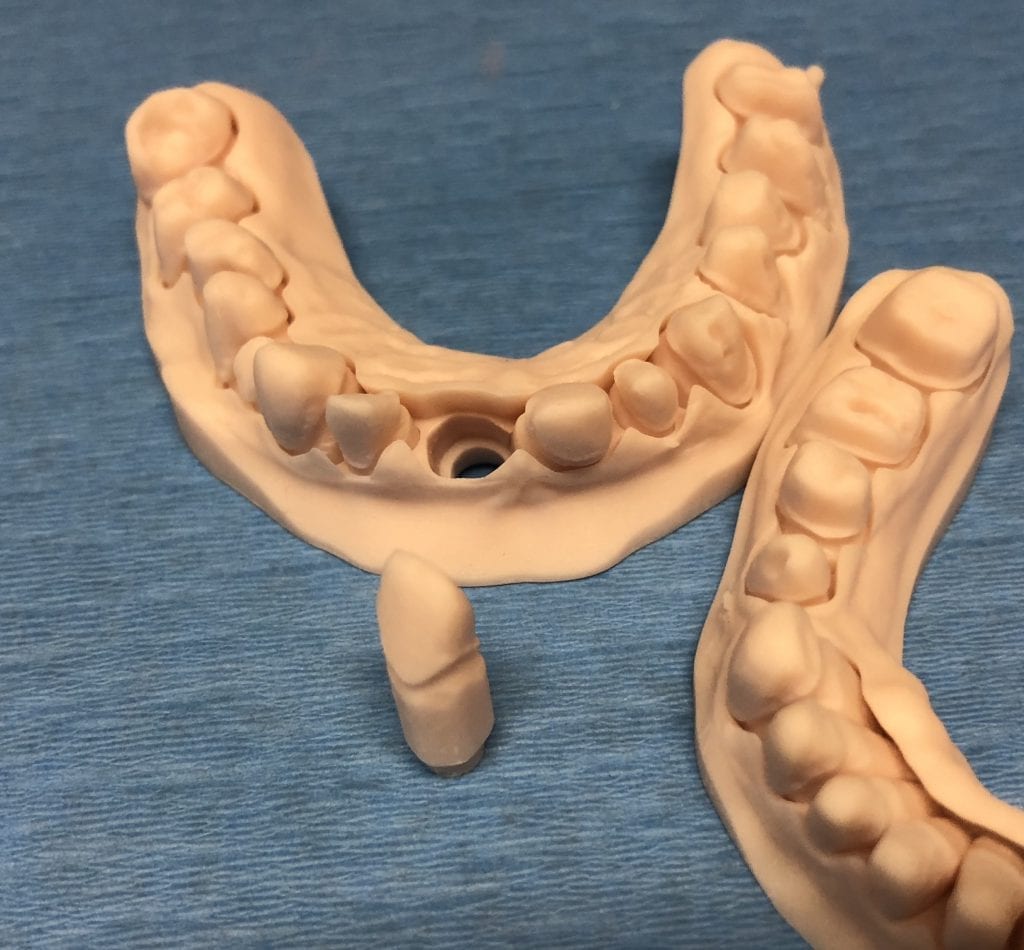

The case was designed by CADENT BESSA, and the models were printed by Burbank Dental Lab with Carbon Printers. There restorations were milled and cut back and layered by Burbank Dental Lab

IMAGES OF PRINTED MODELS